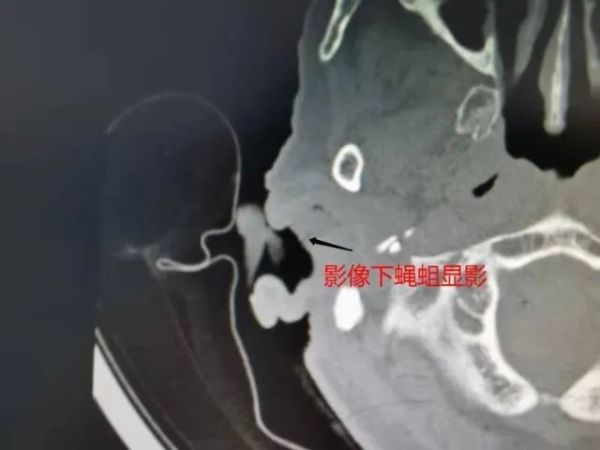

医生让王奶奶完成了其他检查后,决定先为其取出堵塞在耳道里的活体蝇蛆,再做系统的病因分析并制定出行之有效的诊疗方案,从根源上解决疾病。于是医生立刻在视屏耳内镜下进行专业处理,共取出约20余条活体蝇蛆!

耳鼻喉科陈银忠主任医师在详细查阅分析王奶奶的病历后,找到了王奶奶右耳中有蝇蛆的原因——王奶奶右耳外耳道及鼓室存在病灶,引发其右耳反复流脓,招引了苍蝇叮咬产卵,最终导致活体蝇蛆寄生在耳道中(临床中的蝇蛆病)。